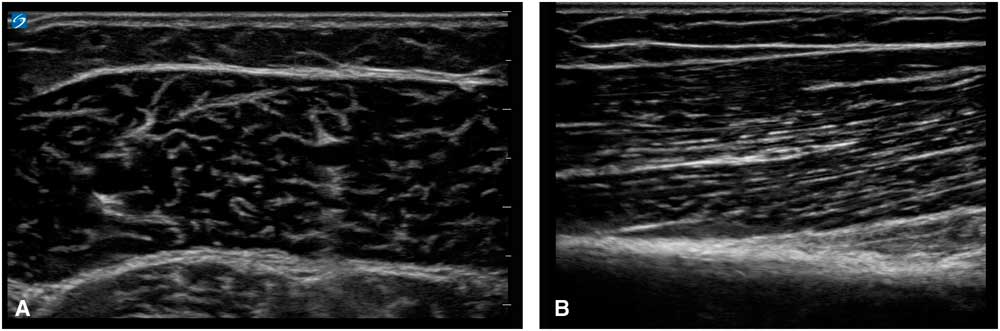

Ultrasound imaging is based on reflections that are created when the ultrasound beam encounters a transition between tissues with different sound velocities and gets reflected back to the transducer. Normal human muscle tissue has relatively few such transitions, which provides a relatively black appearance on the screen. In transverse images, this has been dubbed a “starry night” appearance: a black night sky (the muscle fiber tissue) with speckles that look like stars (the fascia structures; Figure 1A). Longitudinally, the muscle fascicle architecture become visible, which shows as a linear (Figure 1B), bi-pennate or triangular structure in the ultrasound image. Normal peripheral nerves look like round, oval, flat or triangular structures with a white edge (the epineurial rim), filled with black dots of varying sizes (the nerve fascicles; Figure 2A). In a longitudinal view they look like a set of railroad tracks (Figure 2B).

Figure 1 (A) Shows a transverse image of a healthy medial gastrocnemius muscle, showing the “starry night” appearance of dark muscle fiber tissue interspersed with white speckles of fascia. (B) Shows a longitudinal image of a healthy biceps brachii muscle, showing the linear arrangement of muscle fibers that insert at an angle onto the underlying fascia and bone.